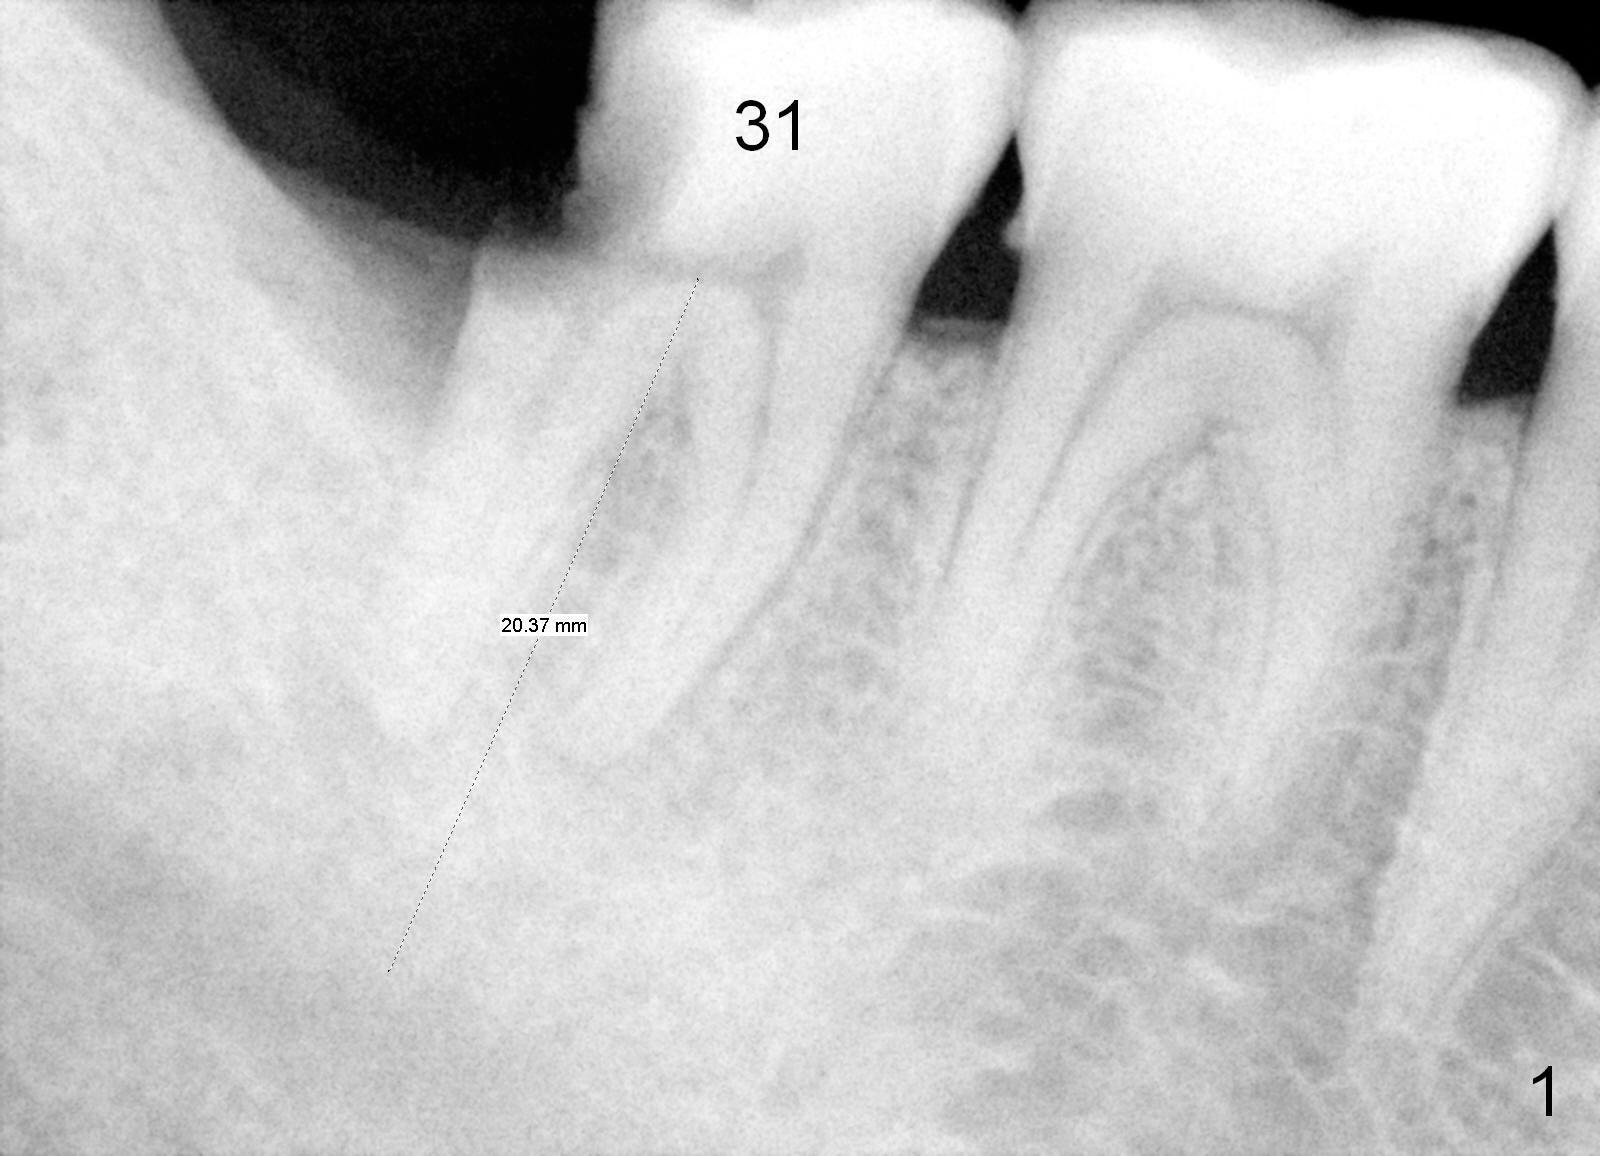

A 45-year-old man has diabetes. His oral hygiene is poor with both caries and chronic periodontitis. Nine years ago, the tooth #31 was non-salvageable (Fig.1). He does not accept treatment readily, especially extraction. At that time, the bone height is 20 mm.